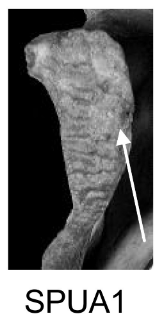

Demi-face postérieure (SPUA)

Changements morphologiques de la demi-face postérieure de la symphyse pubienne, incluant la présence et l'orientation de crêtes et sillons, et le processus de remodelage osseux.